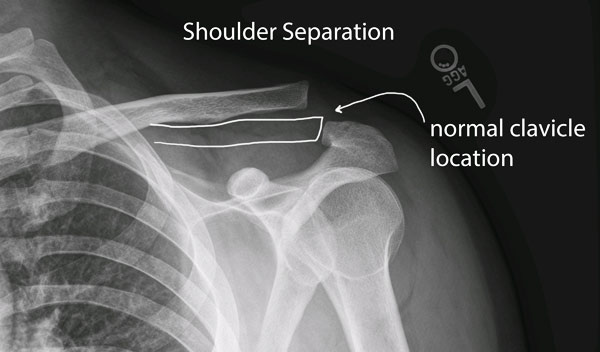

In certain types of clavicle fractures, your clavicle has broken, but its pieces still line up correctly. In other types of fractures (displaced fractures), the injury moves the bone fragments out of alignment.

If you fracture your clavicle, you might need ORIF to bring your bones back into place and help them heal.